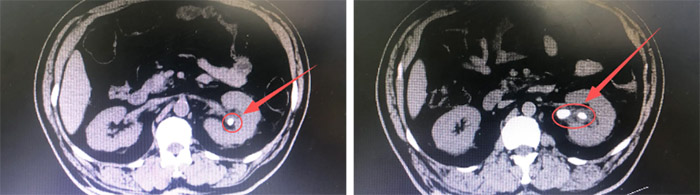

王先生被送到我院就诊时,已经疼得几近晕厥。泌尿系CTU清晰显示:结石分别嵌在肾盂管交界、上下肾盏,最大那枚被炎性息肉紧紧包裹,像颗生锈的螺帽堵死“排水口”,尿液潴留随时可能引发肾衰。手术取石,刻不容缓!